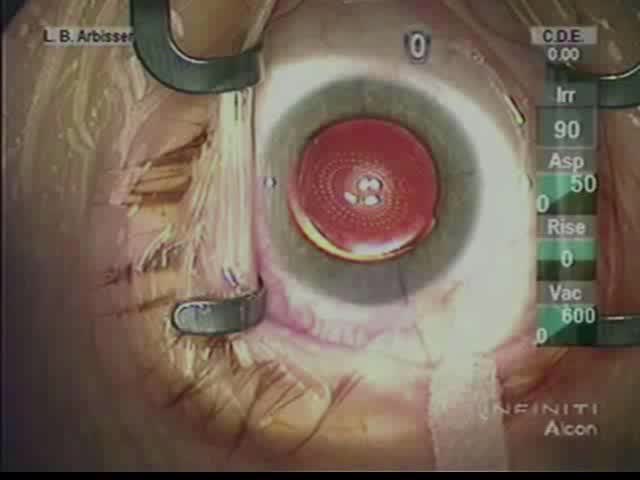

Standard Optic Capture

Lisa Brothers Arbisser, MD